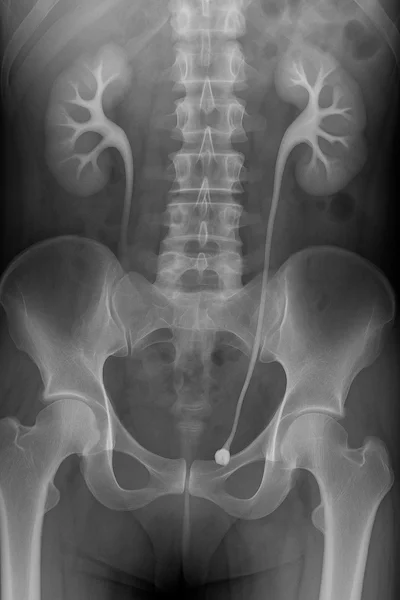

4. Imaging follow-up

Low-dose CT and ultrasound provide stone burden assessment, help track recurrence, and guide surgical referrals when needed. In the nephrology clinic, imaging is also used to detect nephrocalcinosis, which signals chronic metabolic disturbance.

- Imaging with ultrasound or low-dose CT at regular intervals helps detect silent stones before they cause obstruction.